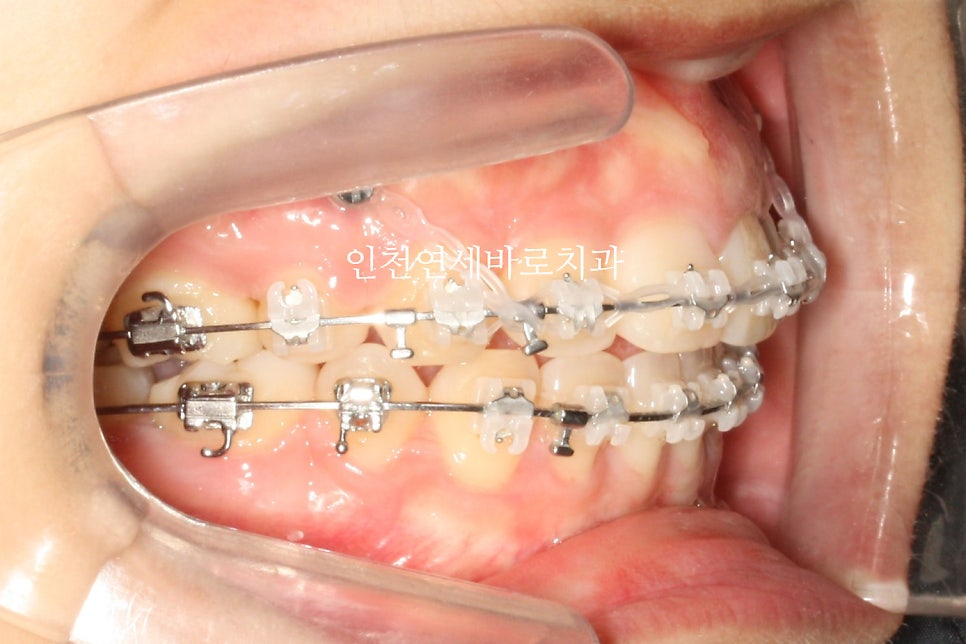

미니스크류를 식립 후 바로 찍은 사진입니다.

총 6개의 미니스크류를 식립하고 치료를 했습니다

미니스크류를 잘 이용하면 얼굴이 짧아지면서 자연스러운 입술을 만들 수 있습니다.

치료기간이 조금 더 긴편이지만, 극적인 안모변화를 얻는 경우가 많습니다